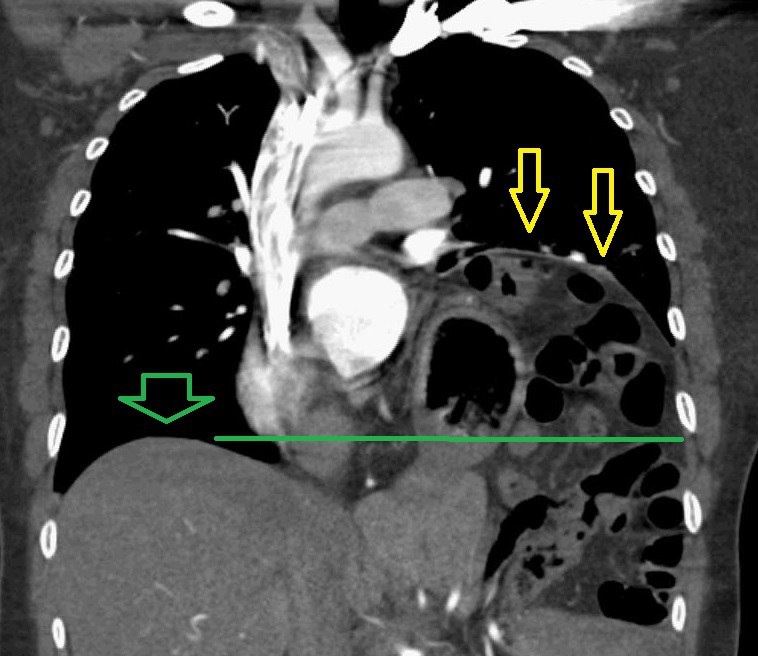

Желтые стрелки подъем левого купола диафрагмы, зеленая и линия это нормальный уровень правого купола